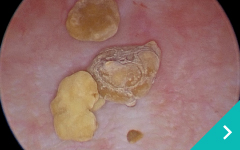

「血液透析」「結石破砕装置」「2.8mm細径内視鏡」 「SUBシステム」「尿管ステント」を組み合わせる事により、今までにない新たな治療に取り組んでいきます。

レーザー結石破砕

レーザー

結石破砕

低侵襲尿管・尿道・膀胱結石治療

低侵襲

尿管・尿道・膀胱結石治療